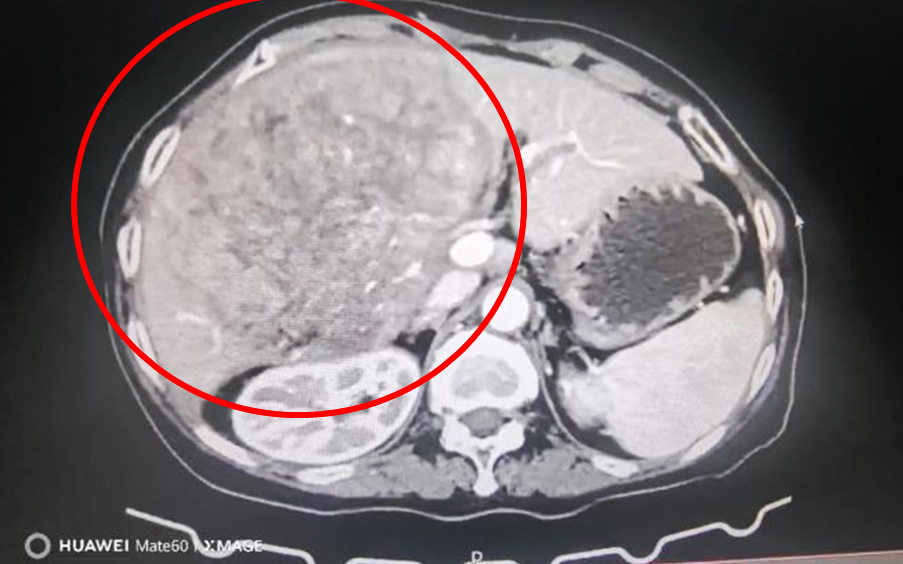

患者程奶奶(化名)因持续腹胀、食欲极差、无法正常进食,身体极度衰弱,紧急来院就诊。肝胆外科副主任周新红接诊后,为其仔细查体,并完善上腹部增强CT检查。影像结果令人揪心,左肝区一枚约20×18cm的巨大占位,向外推挤胃、小肠、结肠及膈肌,向内挤压肝门部重要血管、胆道及门静脉主干,腹腔正常解剖结构已严重变形移位,脏器脆弱、血管变薄,随时可能发生肿瘤破裂导致腹腔内大出血,危及生命。